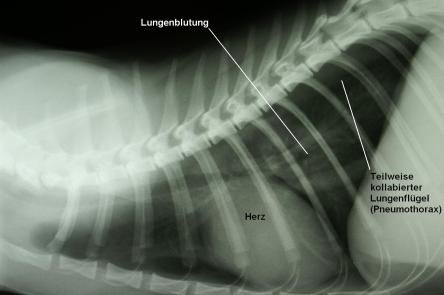

Die Vorgeschichte und Untersuchungsergebnisse sind verdächtig für einen Unfall (z.B. Autounfall). Der Brustkorb wird geröntgt, da bei einem starken Aufprall die Lunge geschädigt werden kann. Auf dem Röntgenbild ist erkennbar, dass eine leichte Lungenblutung stattgefunden hat (Aufhellung im sonst dunklen Lungenfeld) und ein einseitiger Lungenriss vorhanden ist: Die Kontur des einen Lungenflügels ist klar erkennbar, was bedeutet, dass dieser Flügel teilweise kollabiert ist und Luft aus der Lunge in den Raum zwischen Lunge und Brustkorb eingedrungen ist (Pneumothorax). Beide Verletzungen sind relativ gering und bedürfen keiner direkten Therapie.